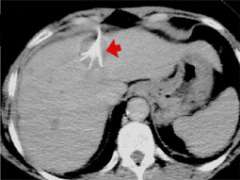

Figure 2: CT images of a liver tumor caused by colon cancer that spreads to the liver, the RFA lesion 1 hour after the treatment, and the scar 6 months after the RFA treatment

To make sure that all tumor cells are destroyed, the ablation is extended beyond the tumor margin by about 0.5 to 1.0 cm. The post-ablation lesion, therefore, is larger than the original tumor size (fig.2). The ablation lesion eventually shrinks into a much smaller scar, if there is no recurrence.